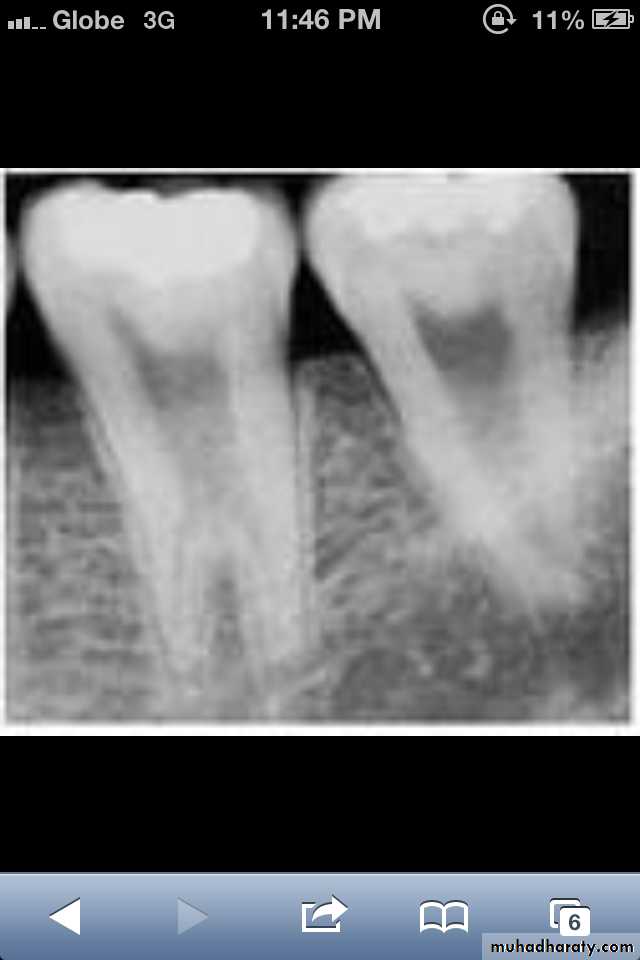

*Taurodont teeth have longitudinally enlarged pulp chambers.

*The crown is of normal shape and size, but the body is elongated and the roots are short.*The pulp chamber extends from a normal position in the crown throughout the length of the extended body, leading to an increased distance between the CEJ and the furcation.

Taurodontism